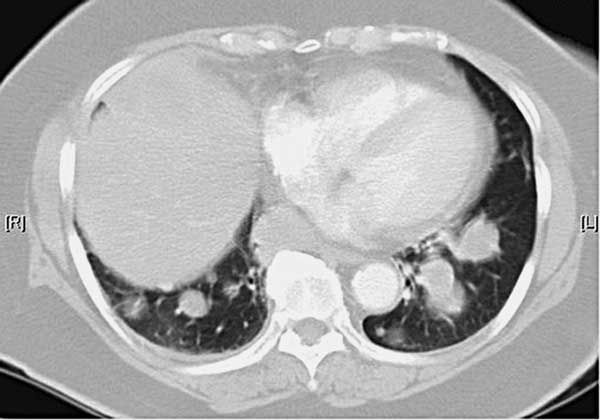

The initial chest radiograph showed multiple pulmonary masses of varying sizes with a large right middle lobe opacity and hilar adenopathy (Figure 1). A CT scan of the chest confirmed a 9.5 × 8.3-cm right middle lobe mass, 3.7 × 2.9-cm and 3.1 × 2.2-cm right lower lobe masses, a 3.6 × 2.0-cm left upper lobe mass, and innumerable diffuse smaller nodules throughout the lung fields (Figure 2).

Figure 2–Multiple “cannonball”-type lesions are seen on this CT scan of the chest.